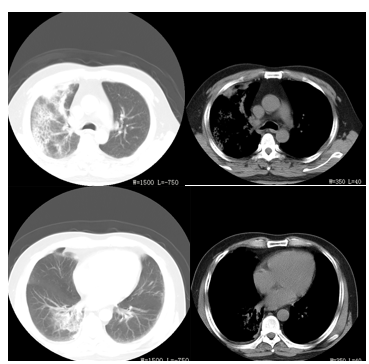

文丘里面罩吸氧(氧浓度50%)监测血氧饱和度为87%,血气分析PH 7.333,PCO2 24.3mmHg,PO2 59.9mmHg,BE -11.15mmol/L,计算氧合指数为119.8。血常规提示WBC 16.4×109/L,N% 87.84%,HBG 120g/L,Pt 174×109/L。血生化酶学:ALT 1612U/L,AST 1080U/L,CK 80998U/L,CK-MB 6610.5U/L,LDH 1157.6U/L,HBDH 1209U/L,MB 1109.2U/L,CTNI 3.75μg/L。血BUN 15.79U/L,Cr 310.4μmol/L,K+3.05mmol/L,Na+135.8mmol/L,Cl-100.7mmol/L,Ca+1.64mmol/L;血TP 44.8g/L,ALB 26g/L,TBIL 12.9μmol/L,DBIL 7.5μmol/L,IBIL 5.4μmol/L;血BNP 23.3pg/ml。凝血全项PT 13.6秒,PTA 76%,APTT 30.6秒,DD 3.8mmol/L ;血清嗜肺军团菌抗体阳性(间接免疫荧光法),尿军团菌抗原阳性;心电图提示窦性心动过速,V3、V4 ST段抬高。胸CT示肺纹理增多紊乱,右肺见片状模糊影(图9-1A、9-1B、9-1C、9-1D)。

图9-1A、9-1B、9-1C、9-1D 2015-6-20胸CT 右肺见片状模糊影